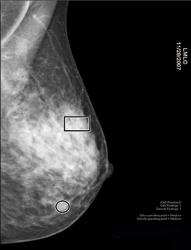

Mammogram Question 40 years old and had mammogram This is what the report says Breast parenchyma is heterogeneously dense Focal asymmetry seen in upper central right breast which cannot be confirmed as stable Additionally, an asymmetry in the superior right breast, posterior depth which appears more prominent when compared to prior studies Dense breast tissue is a normal finding, and about half of all women have dense breast tissue If you have dense breast tissue, this means you have a higher proportion of glandular breast tissue to fatty tissue Having dense breast tissue can make it more difficult to see breast cancer on a mammogram Dense tissue appears white on a mammogram while fatty tissue appears black Breast One of the main problems with dense breast tissue is that it shows up as white on mammogram images Fatty breast tissue looks black in images Unfortunately, signs of breast cancer like tumors or calcifications also appear white in mammograms, making it difficult for doctors to detect abnormalities Additional breast screening techniques may be required to get a true picture of your breast

Breast lesions are not easily discernible in these areas since dense tissue and tumors both look white on film Understanding how dense breasts affect cancer risk remains a problem of standardization, said Celia Byrne, PhD, Harvard Medical School, Cambridge, Mass No one method of measuring breast density has been agreed upon The 21 edition of ICD10CM N64 became effective on This is the American ICD10CM version of N64 other international versions of ICD10 N64 may differ Single or multiple, milkcontaining nodules in the breast It is caused by obstruction of the breast ducts during lactation Breast Parenchyma Is Heterogeneously Dense Yes a homogeneously dense breast on mammogram or ultrasound usually means that nothing is standing out suspiciously This can make it hard to see small tumors in or around the dense tissue Your Patient Got A Dense Breast Notification With Her Mammogram Report What Are You Supposed To Do Christianacare News

Newer technology known as digital breast tomosynthesis (DBT), sometimes called threedimensional (3D) mammography, appears to be more accurate than traditional 2D mammography for women with heterogeneously dense breasts Like traditional mammography, 3D mammography takes two views of each breast, but then creates images of thin slices of the breast tissue for the radiologist to read These slices are somewhat like a CT scan result, showing slivers of the breastThis means that you have moderately dense tissue, which is common and not a cause for concernBreast Parenchyma/Heterogenously dense Lilly1313 I just received the results of a mammogram and the findings state the following "The breast parenchyma is heterogenously dense There is a 12mm nodule in the upper inner quadrant of the right breast The border appears well defined, however is partially obscured

Lumps, both benign and cancerous, also appear white So, mammograms can be less accurate in women with dense breasts If a woman's mammogram shows she has heterogeneously dense or extremely dense breast tissue, sheIII The breast is heterogeneously dense This may lower the sensitivity of mammography IV The breast tissue is extremely dense, which could obscure a lesion in mammography Examples of these breast types are shown in Figure 1 Other pattern classifications include the sixcategory classification (SCC)There are four descriptors for breast density on mammography in the 5 th edition of BIRADS 1,2 a the breasts are almost entirely fatty b there are scattered areas of fibroglandular density c the breasts are heterogeneously dense, which may obscure small masses d the breasts are extremely dense, which lowers the sensitivity of mammography